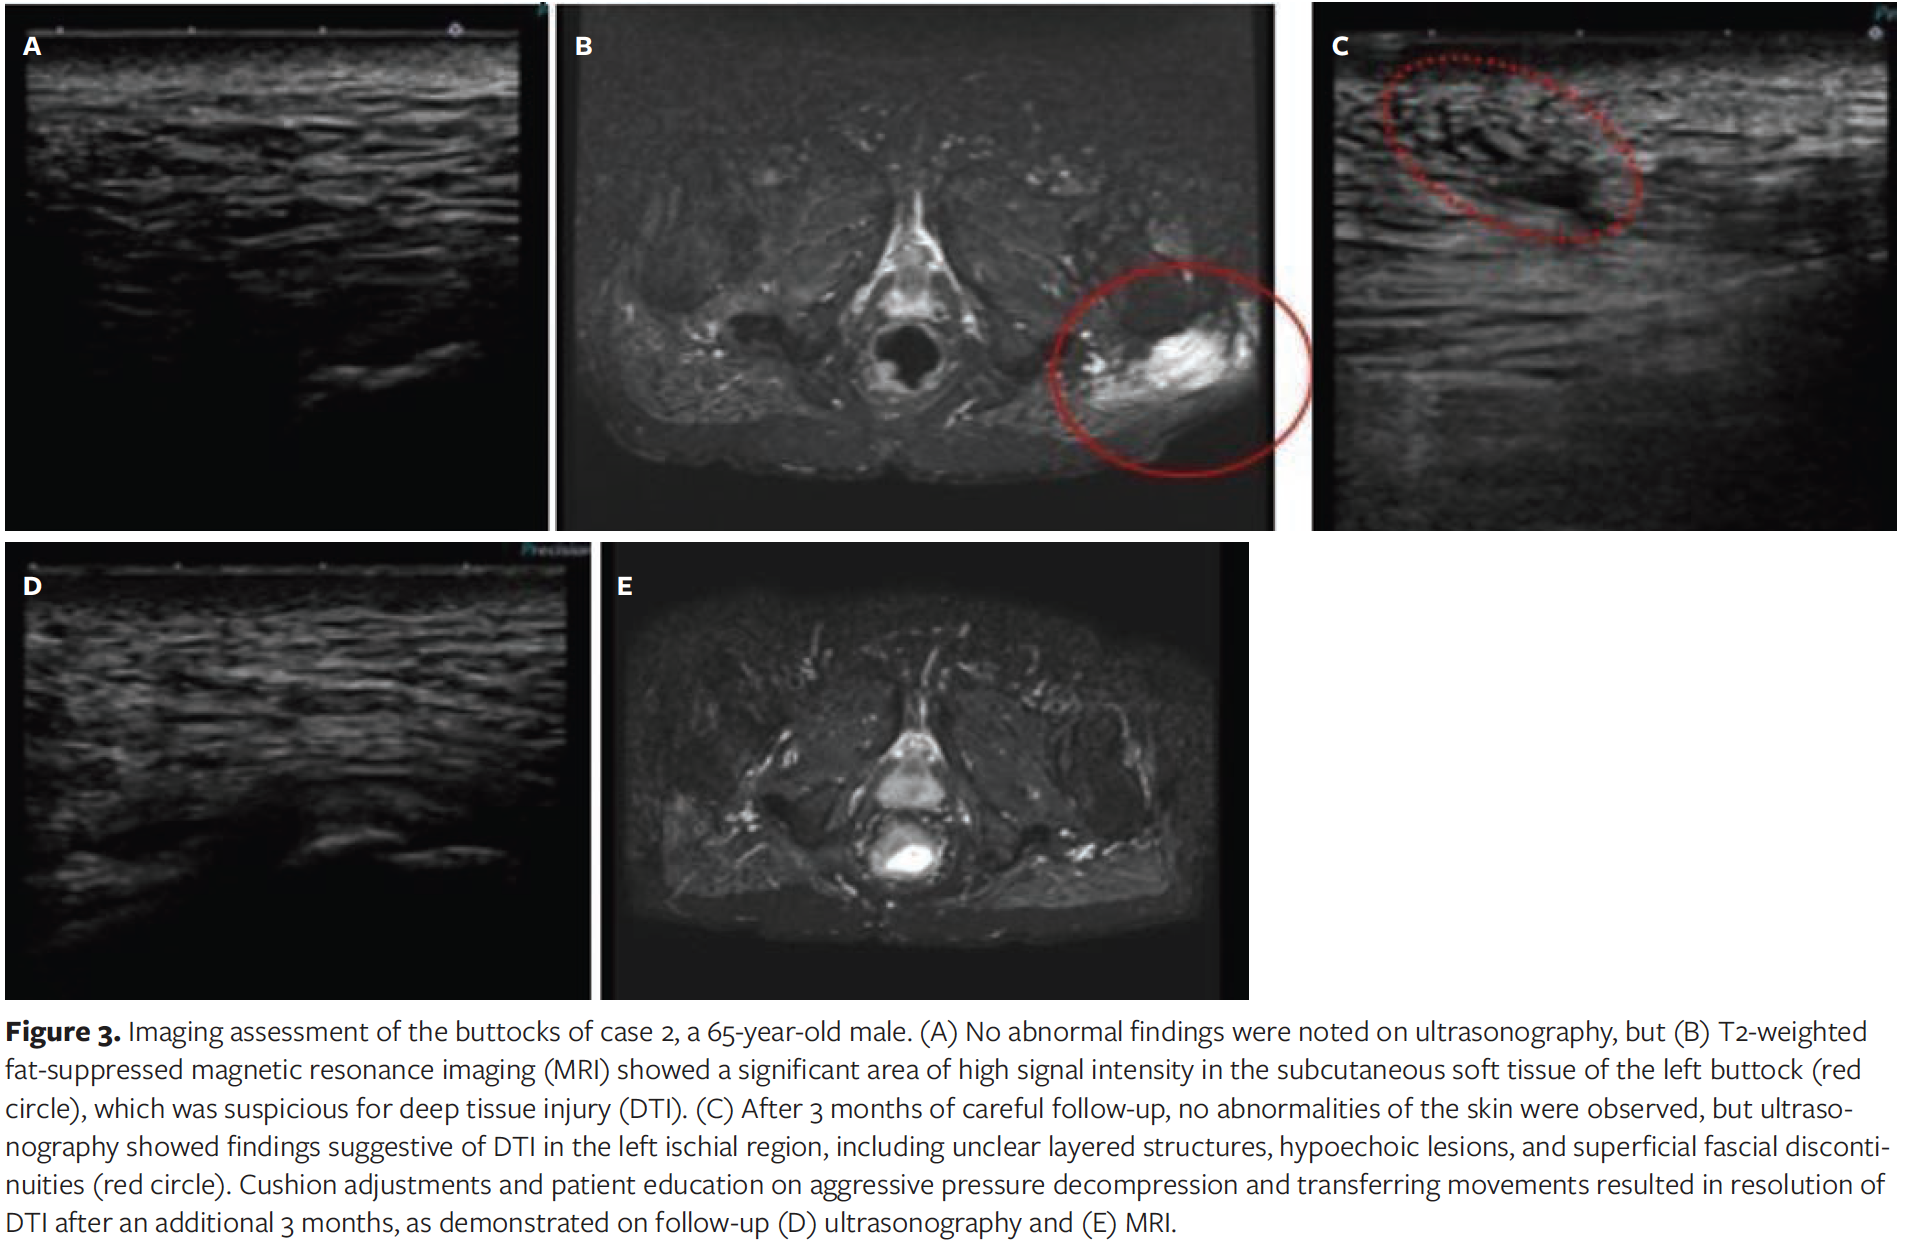

A 65-year-old male with complete paraplegia (American Spinal Injury Association Impairment Scale type A injury) at the T1 level resulting from a fall 9 years previously was admitted to Kibikogen Rehabilitation Center for Employment Injuries for a lower gastrointestinal endoscopy as a routine medical checkup. Physical examination on admission revealed no skin abnormalities on either buttock. The patient had been in a wheelchair 15 hours a day for the past year and, because of his obesity, had difficulty pushing himself up from the chair for decompression. The interface pressure measurements were 264 gf/cm2 for the left ischial region and 179 gf/cm2 for the right ischial region with the patient using an air cell-based high-profile cushion while seated in his wheelchair. The left ischial region had higher pressure and thus, was considered to be at higher risk of DTI. Because of the patient’s obesity and the thick subcutaneous soft tissue, and the perceived difficulty of screening for DTI by assessing deep tissue by ultrasonography only, MRI was also performed. Ultrasonography showed no abnormal findings (Figure 3A). However, T2-weighted fat-suppressed MRI showed a significant area of high signal intensity in the subcutaneous soft tissue of the left buttock, which was suspicious for DTI (Figure 3B).

After 3 months of careful follow-up, no abnormalities were apparent based on external appearance of the skin; however, ultrasonography showed findings suggestive of DTI in the left ischial region, including unclear layered structures, hypoechoic lesions, and superficial fascial discontinuities (Figure 3C). After a further 3 months of cushion adjustment and teaching the patient aggressive decompression and transferring movements, resolution of DTI was observed on both ultrasonography and MRI (Figure 3D, 3E).

The characteristic ultrasonographic findings of DTI consist of an unclear layered structure, a hypoechoic lesion, discontinuous superficial or deep fascia, and a heterogeneous hypoechoic area.10 In particular, the presence of discontinuous deep fascia or heterogeneous hypoechoic areas are particularly concerning for DTI.10 In the current case report, although there was no abnormality on the skin surface in either case 1 or case 2, both patients had ultrasonographic characteristics of DTI as well as discontinuous fascia, and the authors of the current report were concerned that DTI could worsen in the future. In contrast, findings suggestive of DTI were observed on T2-weighted fat-suppressed MRIs, which clearly showed regions of high signal intensity in the subcutaneous soft tissues below the bone. In case 1, MRI findings showed abnormal shadows from both ischial tuberosities to the subcutaneous tissue, confirming the bottom-up theory of the progression of DTI development from the deep layers to the superficial skin as discussed in Ankrom et al.25 In case 2, MRI showed extensive abnormal shadows in the subcutaneous soft tissue of the left buttock. This finding is similar to that of a previously reported case of DTI in the thigh that was confirmed by MRI.13

Further supporting the use of MRI, in case 2, abnormal findings were detected by MRI 3 months before features of DTI were identified by ultrasonography. Although obesity and thick subcutaneous soft tissue may have made it difficult to detect DTI on ultrasonography in this patient, abnormal findings were clearly identified on MRI, suggesting that deeper tissue can be visualized earlier by MRI than by ultrasonography. Consequently, the authors of the current report propose that MRI may be superior to ultrasonography for detecting DTI and that use of MRI would lead to earlier intervention and healing. In practice, MRI is sometimes disregarded because of the high cost (approximately $350 as of 2019 in the United States according to Medicare reimbursement data, depending on the facility) and lengthy examination time.26 However, in terms of the economic burden of DTI, 11% to 26% of DTI cases reportedly progress to deep pressure ulcers,27,28 and a 2007 publication reported that DTI costs up to $70 000 per case for surgical and medical treatment when it progresses to full-thickness pressure ulcers.29 Thus, the authors of the current report propose that MRI could be a screening tool for patients with spinal cord injury who are at high risk for DTI, with the understanding that MRI may not be appropriate for every patient.